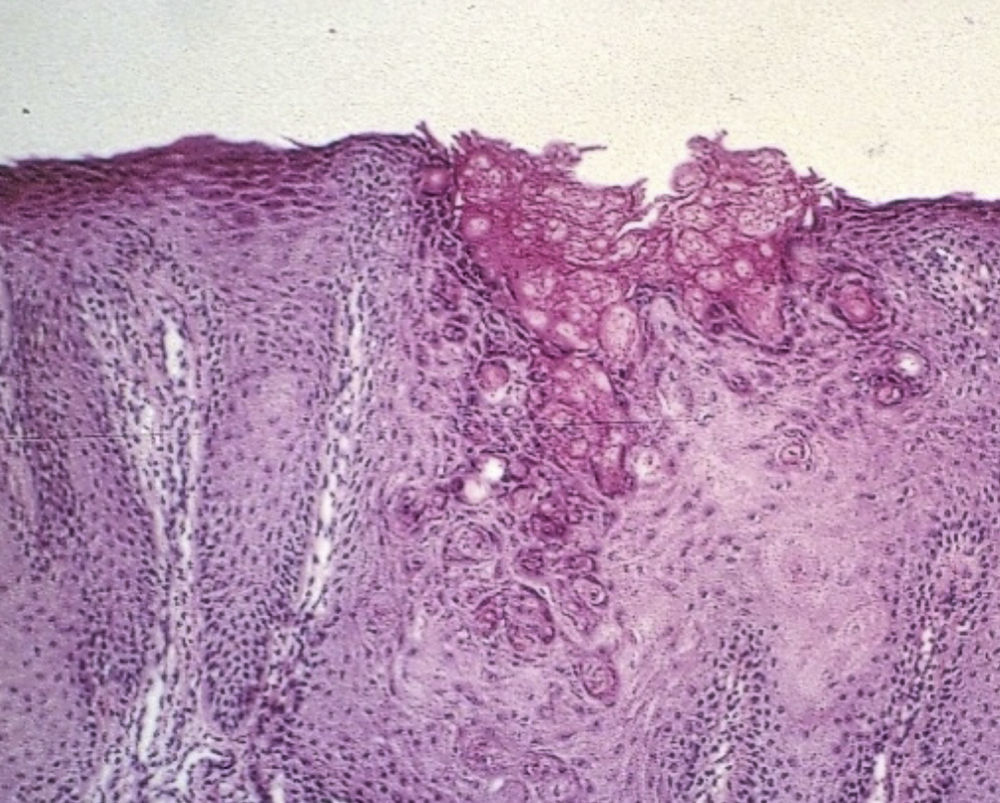

El signo de Leser-Trélat se caracteriza por la aparición súbita y el rápido crecimiento en número y tamaño de múltiples queratosis seborreicas, relacionado con una neoplasia subyacente. Masculino de 57 años de edad, con 4 meses de evolución con cambios en hábitos defecatorios, refiriendo adelgazamiento de las evacuaciones, así como la presencia de rectorragia ocasional con manchado lineal de las evacuaciones, asociado a esto refiere la aparición de hace un año de lesiones dérmicas en su espalda que aparecieron súbitamente y se incrementaron en número. En la colonoscopia con lesión circunferencial a 13cm del margen anal (fig. 1) con reporte histopatológico de adenocarcinoma. En la espalda del paciente (fig. 2), se aprecian múltiples lesiones dérmicas de las que se toma biopsia reportándose queratosis seborreica (fig. 3).

El signo de Leser-Trélat es definido como el inicio abrupto, con incremento rápido del tamaño o el número, de múltiples queratosis seborreicas asociadas a un cáncer. La presencia de lesiones de queratosis seborreica con aparición repentina, lesiones pigmentadas y en gran número deben de alertar al clínico para descartar otras entidades y asociaciones a otras lesiones como neoplasias. La biopsia de las lesiones dérmicas confirma el diagnóstico.